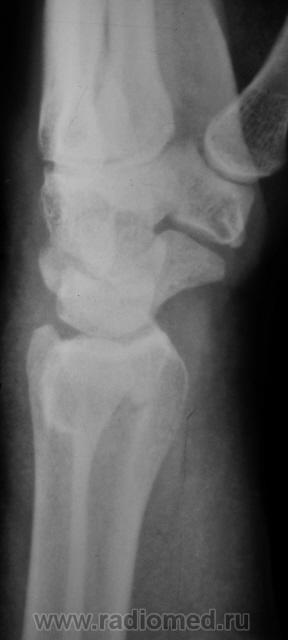

Пол пациента: Мужской пол Тип патологии: Травма Область исследования: Скелетно-мышечная система Методы исследования: Rg Травма. Пациент направлен врачом хирургом на рентгенографию лучезапястного сустава. Произведено исследование. Ваше мнение коллеги? Thu, 15/10/2009 - 21:47 #1 Наталия Offline Last seen: 8 years 8 months ago Joined: 30.07.2008 - 13:24 Posts: 538 Откол части шиловидного отростка локтевой кости, перелом лучевой кости в питичном месте, перелом ладьевидной кости. Может отрыв крючка. Thu, 15/10/2009 - 22:25 #2 v1tal Offline Last seen: 4 years 10 months ago Joined: 07.06.2008 - 19:41 Posts: 1779 Можно добавить краевой перелом кости-трапеции. "Знаешь, у некоторых врачей есть комплекс мессии — им необходимо спасать мир. А у тебя комплекс Рубика — тебе необходимо решать головоломки." Sun, 18/10/2009 - 23:33 #3 Катенёв Валенти... Offline Last seen: 7 years 1 month ago Joined: 22.03.2008 - 22:15 Posts: 54876 Так выходит - 3 перелома!? Mon, 19/10/2009 - 20:15 #4 Анатолий Владим... Offline Last seen: 7 years 11 months ago Joined: 16.10.2009 - 21:16 Posts: 1941 В ладьевидной кости в норме часто можно наблюдать ступеньку по наружному контуру, которая симулирует перелом. Для окончательного решения вопроса необходима рентгенограмма костей запястья в косой проекции.

Откол части шиловидного отростка локтевой кости, перелом лучевой кости в питичном месте, перелом ладьевидной кости. Может отрыв крючка.

Можно добавить краевой перелом кости-трапеции.

Так выходит - 3 перелома!?

В ладьевидной кости в норме часто можно наблюдать ступеньку по наружному контуру, которая симулирует перелом. Для окончательного решения вопроса необходима рентгенограмма костей запястья в косой проекции.